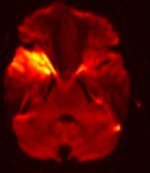

MR-Angiographie (MRA) meiner Halsgefäße |

Zwei Arterienpaare übernehmen die Blutzufuhr zum Gehirn (Arteria

carotis interna) und (Arteria vertebralis).

Beide vereinigen sich in der Hirnbasis zu einem

ringförmigen Arterienkreis, dem Circulus Willisii. Vom

Willisi-Kreis gehen paarweise die drei großen Hirnarterien ab,

die vordere, mittlere und hintere Hirnarterie. |

MR-Angiographie (MRA) meiner

Hirnbasisarterien

(Circulus Willisi) |

gut sichtbar distale Stenose Arteria

carotis rechts |